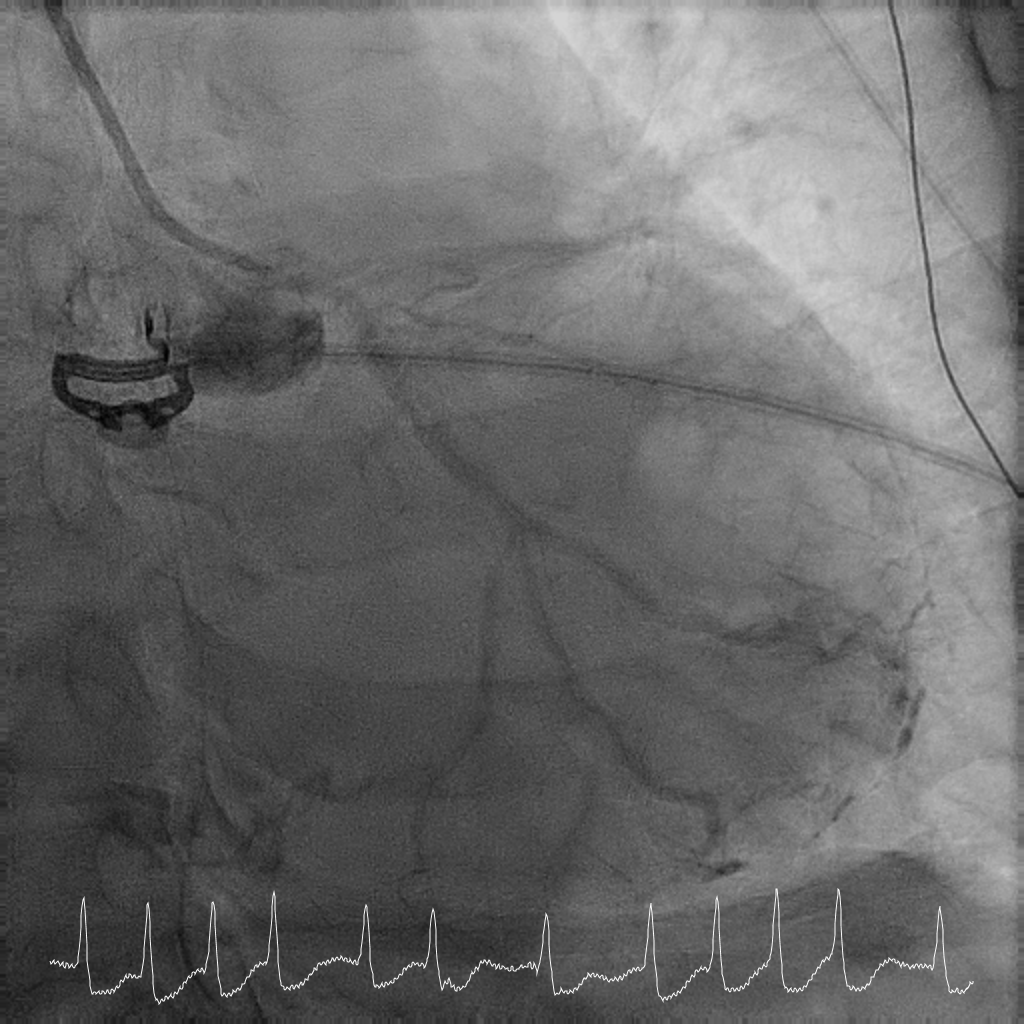

Coronary angiography showed critical calcified LM into both LAD and LCx. LAD was noted to be calcified and occluded at the ostium, with collaterals from LCx filling the distal LAD. RCA was a long segment CTO (occluded at the ostium) and showed retrograde filling from LCx collaterals. There was moderate proximal disease of the LCx. Cardiac surgery was consulted for consideration of urgent CABG, but surgical risk was prohibitive. After discussion with family, decision was for high-risk complex PCI.

Rotational atherectomy with 1.5mm and then 2mm was performedfrom ostial LM to proximal LCx. Wiring of the LAD was only successful till midLAD with a separate distal LAD occlusion. LAD lesion was balloon uncrossableand half-way rotational atherectomy with 1.5mm burr. The distal LAD CTO wasthen crossed and balloon angioplasty undertaken. There was diffuse LAD disease, and the plan was then for ahybrid strategy. PCI to LM bifurcation was secured using the DK crushtechnique. 3.5x23mm Xience Sierra was placed in the LCx, 3.5x16mm Megatron inLM to proximal LAD followed by drug coated balloon angioplasty for the rest ofthe LAD with 2x40mm, 2.5x40mm, and 3x25mm balloon. She recovered well after her intervention and is infunctional New York Heart Association Class I, Canadian Cardiovascular Society Angina Grade 0. An elective angiogram was performed 6 months after indexprocedure to re-assess the results. This showed widely patient stents acrossthe LM-LAD-LCX, and excellent DCB results across the proximal to distal LAD andimprovement of her left ventricular ejection fraction.